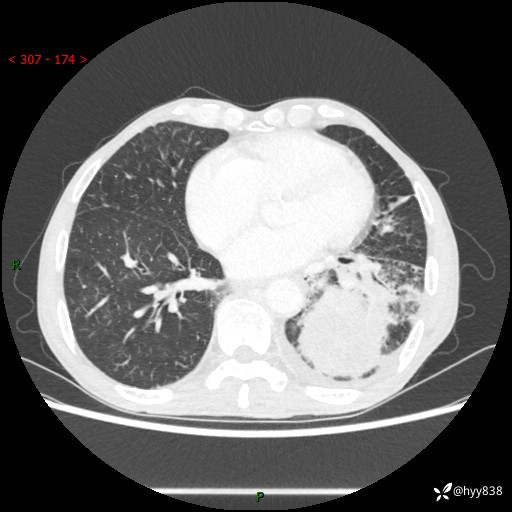

77岁/男,腹痛2月,CT发现左肺占位1天。巨大肿块,肺内或肺外来源…结果公布~

主诉:腹痛2月,CT发现左肺占位1天

现病史:患者于2025年9月间断左下腹胀痛,在当地镇卫生院行彩超检查考虑泌尿系结石,行止痛排石对症治疗未见明显好转;1天前腹痛症状加重,至当地市第三人民医院行CT检查:左肺下叶巨大团块状软组织影,考虑肿瘤性病变,建议增强CT检查;左侧胸腔积液;纵膈内淋巴结肿大;双肺肺气肿;右肺中叶纤维灶。为进一步求治,来我院就诊。

胸部CT平扫+增强